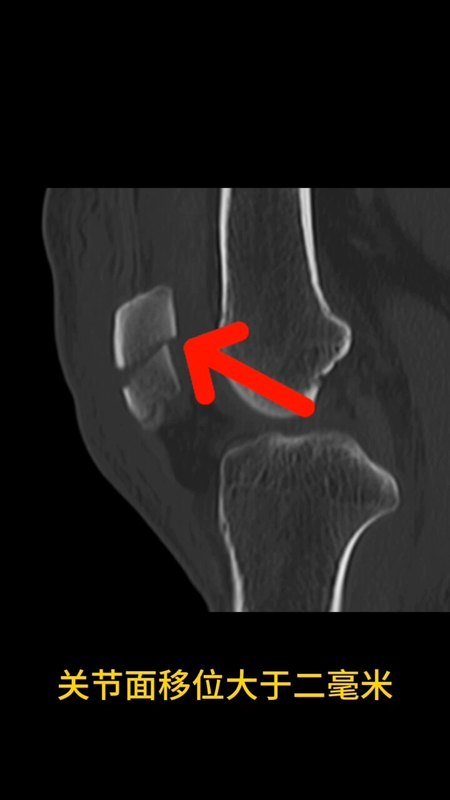

过年期间,很多人都趁着假期出门游玩,爬山、逛庙,“讨”红包。但是,一定要注意安全。最近科里来了3个骨折病人,都是髌骨骨折。髌骨骨折大约占全身骨折的1%,患者以20~50岁的中青年为主。髌骨骨折主要由直接或间接暴力作用于膝关节前侧引起,导致不同程度的骨折移位以及股四头肌腱损伤。1、非手术治疗的指征,包括无移位的骨折以及伸肌装置无损伤。也包括因麻醉限制而无法实施手术的患者,或者不愿接受手术治疗的患者。在针对髌骨骨折的保守治疗中,需要采用过膝的管型石膏或者夹板固定4~6周,并辅以循序渐进的恢复性锻炼。对于采取保守治疗的患者,应提醒其疗效可能不理想。2、所有移位的髌骨骨折都具备手术治疗的指征。骨折粉碎伴随关节面损伤,软骨骨折伴关节内游离体,开放性骨折,以及所有伴有同侧肢体骨折的患者,都应采取手术治疗来达到早期活动的目的。